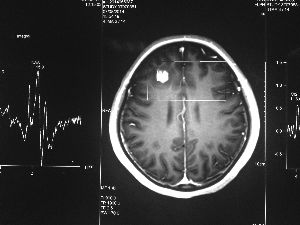

方框亮點為CT片顯示的異物

今年6月份,張敏在宿舍休息時,又發(fā)起了癲癇,也是口吐白沫,渾身抽搐。送到蘇州一家大醫(yī)院,頭顱核磁共振檢查出,張敏大腦右額葉處有一處病灶,也就是大腦額頭處有個東西。

專家認為有可能是腦瘤,但也有可能是其他的東西,具體是什么,卻沒有辦法進一步判斷。醫(yī)院開了一點控制癲癇的藥物,讓張敏服用,并叮囑隨時復查。

腦袋里的東西,到底是腫瘤還是其他什么東西,這個謎像個石頭一樣,壓得張敏一家人喘不過氣。7月份,張敏一家又來到南京腦科醫(yī)院求醫(yī),第三次檢查后,醫(yī)生覺得很像是寄生蟲。不過,影像的檢查,只能作為醫(yī)生推測的依據(jù),具體是什么,只有手術拿出來后才能知道。